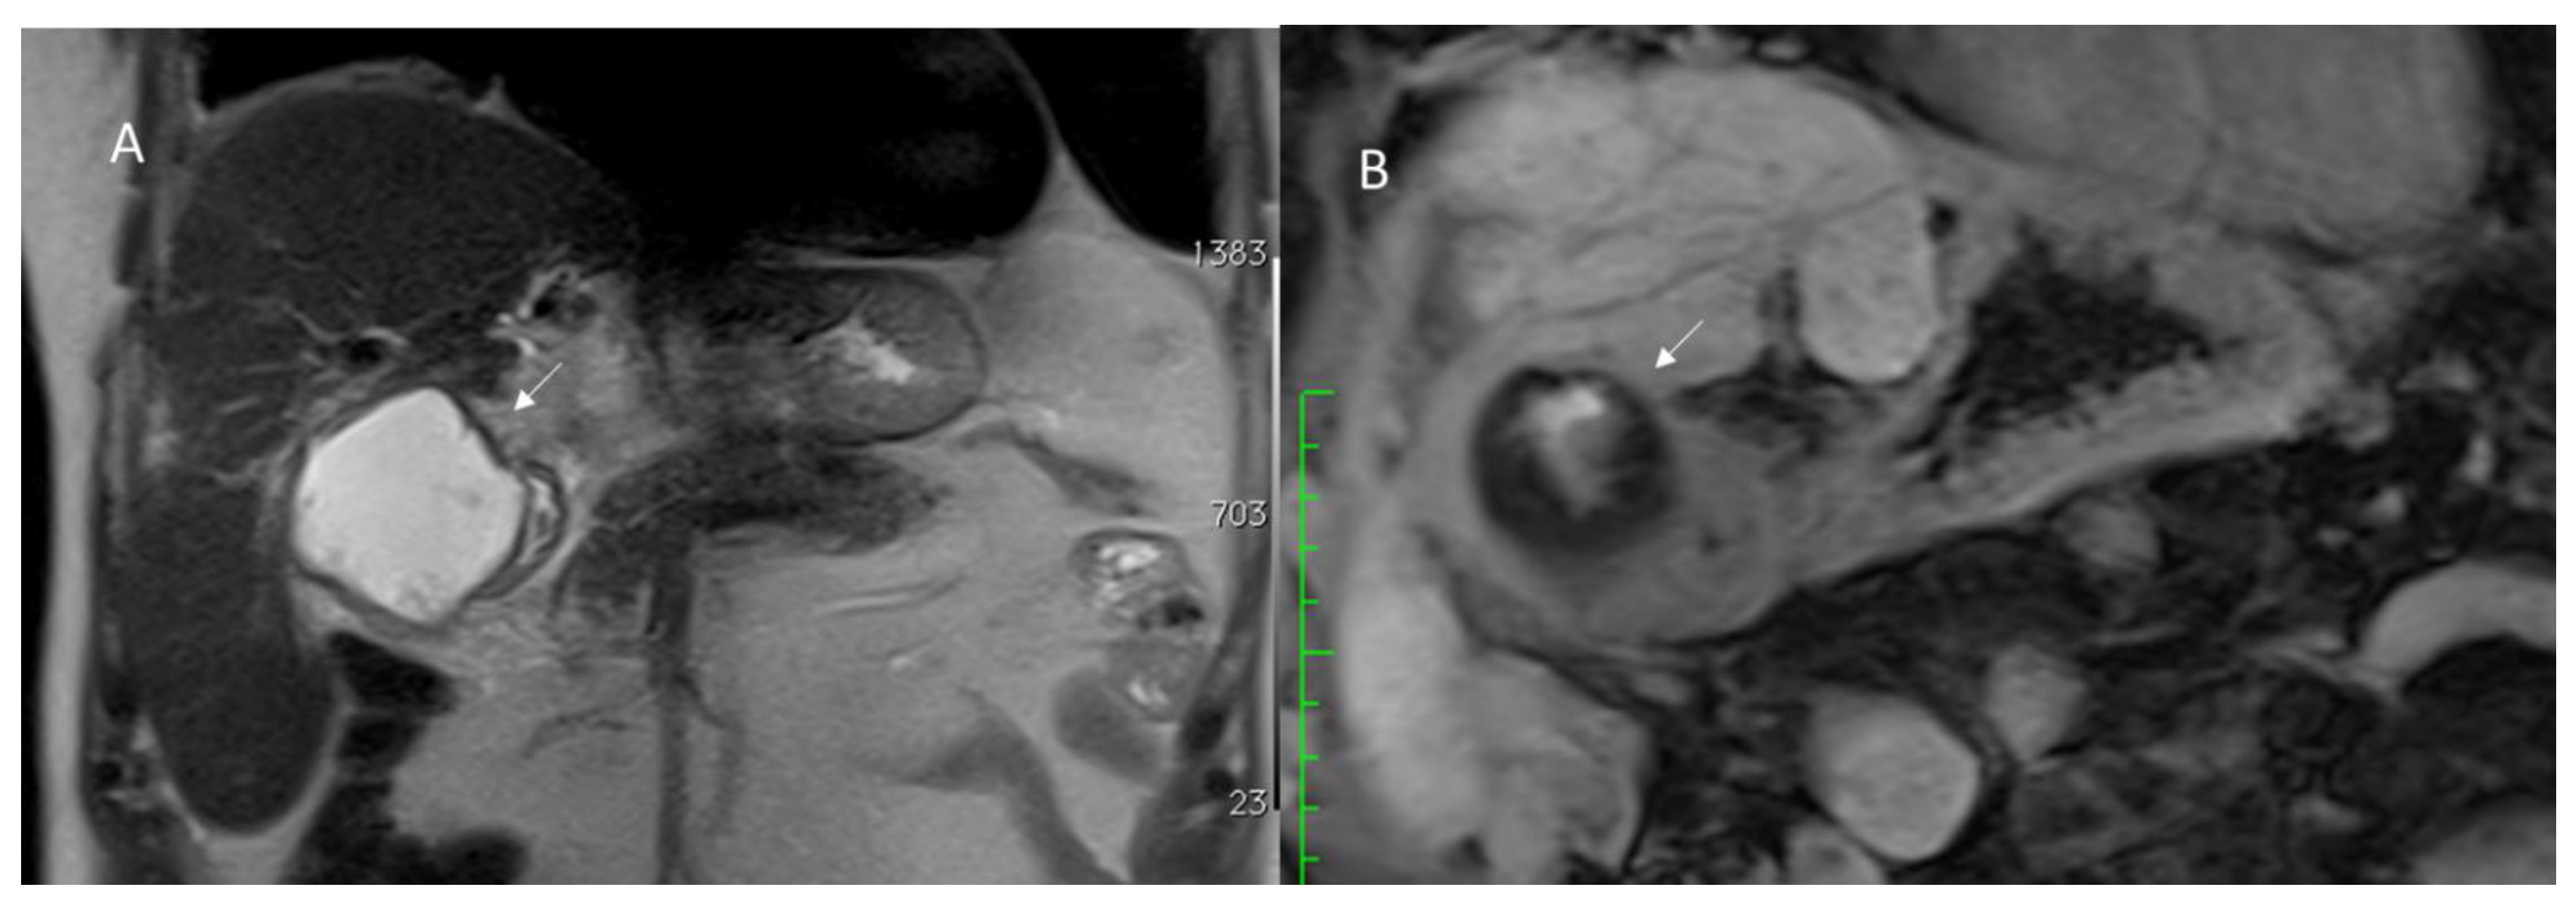

3.1.3. Vascular Thrombosis

- Di Domenico, S.; Rossini, A.; Petrocelli, F.; Valente, U.; Ferro, C. Recurrent acute Budd-Chiari syndrome after right hepatectomy: US color-Doppler vascular pattern and left hepatic vein stenting for treatment. Abdom. Imaging 2013, 38, 320–323. [Google Scholar] [CrossRef]

- Yoshiya, S.; Shirabe, K.; Nakagawara, H.; Soejima, Y.; Yoshizumi, T.; Ikegami, T.; Yamashita, Y.; Harimoto, N.; Nishie, A.; Yamanaka, T.; et al. Portal vein thrombosis after hepatectomy. World J. Surg. 2014, 38, 1491–1497. [Google Scholar] [CrossRef]

- Cohen, J.; Edelman, R.R.; Chopra, S. Portal vein thrombosis: A review. Am. J. Med. 1992, 92, 173–182. [Google Scholar] [CrossRef]

- Witte, C.L.; Brewer, M.L.; Witte, M.H.; Pond, G.B. Protean manifestations of pylethrombosis. A review of thirty-four patients. Ann. Surg. 1985, 202, 191–202. [Google Scholar] [CrossRef] [PubMed]

- Sheen, C.L.; Lamparelli, H.; Milne, A.; Green, I.; Ramage, J.K. Clinical features, diagnosis and outcome of acute portal vein thrombosis. QJM 2000, 93, 531–534. [Google Scholar] [CrossRef] [PubMed]

- Sakuraba, M.; Miyamoto, S.; Nagamatsu, S.; Kayano, S.; Taji, M.; Kinoshita, T.; Kosuge, T.; Kimata, Y. Hepatic artery reconstruction following ablative surgery for hepatobiliary and pancreatic malignancies. Eur. J. Surg. Oncol. 2012, 38, 580–585. [Google Scholar] [CrossRef]

- Silva, M.A.; Jambulingam, P.S.; Gunson, B.K.; Mayer, D.; Buckels, J.A.; Mirza, D.F.; Bramhall, S.R. Hepatic artery thrombosis following orthotopic liver transplantation: A 10-year experience from a single centre in the United Kingdom. Liver Transpl. 2006, 12, 146–151. [Google Scholar] [CrossRef]

- Bhattacharjya, S.; Gunson, B.K.; Mirza, D.F.; Mayer, D.A.; Buckels, J.A.; McMaster, P.; Neuberger, J.M. Delayed hepatic artery thrombosis in adult orthotopic liver transplantation—A 12-year experience. Transplantation 2001, 71, 1592–1596. [Google Scholar] [CrossRef]

- McNaughton, D.A.; Abu-Yousef, M.M. Doppler US of the liver made simple. Radiographics 2011, 31, 161–188, Erratum in Radiographics 2011, 31, 904. [Google Scholar] [CrossRef]

- Ralls, P.W.; Johnson, M.B.; Radin, D.R.; Boswell, W.D., Jr.; Lee, K.P.; Halls, J.M. Budd-Chiari syndrome: Detection with color Doppler sonography. AJR Am. J. Roentgenol. 1992, 159, 113–116. [Google Scholar] [CrossRef][Green Version]